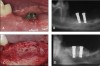

Figure 2   rhPDGF promotes extensive vertical and lateral bone formation in a large, chronic critical sized alveolar ridge defect (3cm long x 7 mm to10 mm deep x the entire width of the mandible) model in canines. The upper panels (2A and 2B) represent the clinical and radiographic out- comes 4 months after treatment using an earlier standard of care consisting of a guided bone regeneration (GBR) procedure that utilized a deproteinized bovine bone block covered by a cell occlusive collagen membrane. Virtually no vertical bone augmentation was achieved. The lower panels (2C and 2D) represent the clinical reentry and radiographic results 4 months following treatment using rhPDGF infused in the deproteinized bovine block without a membrane. High quality dense bone was regenerated throughout the defect, both vertically and horizontally.30

Figure 2